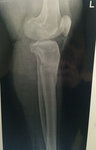

Ножки супер! разрешено всё без ограничений, все нагрузки: спорт, фитнес, каблуки любых размеров - Вам очень они пойдут! Нельзя: беременеть в течении первых 6 месяцев с момента снятия аппаратов!

Не забывайте про наш форум, высылайте фото ножек, пишите отзывы, нам это важно, это наша работа - искусство, которым мы гордимся!